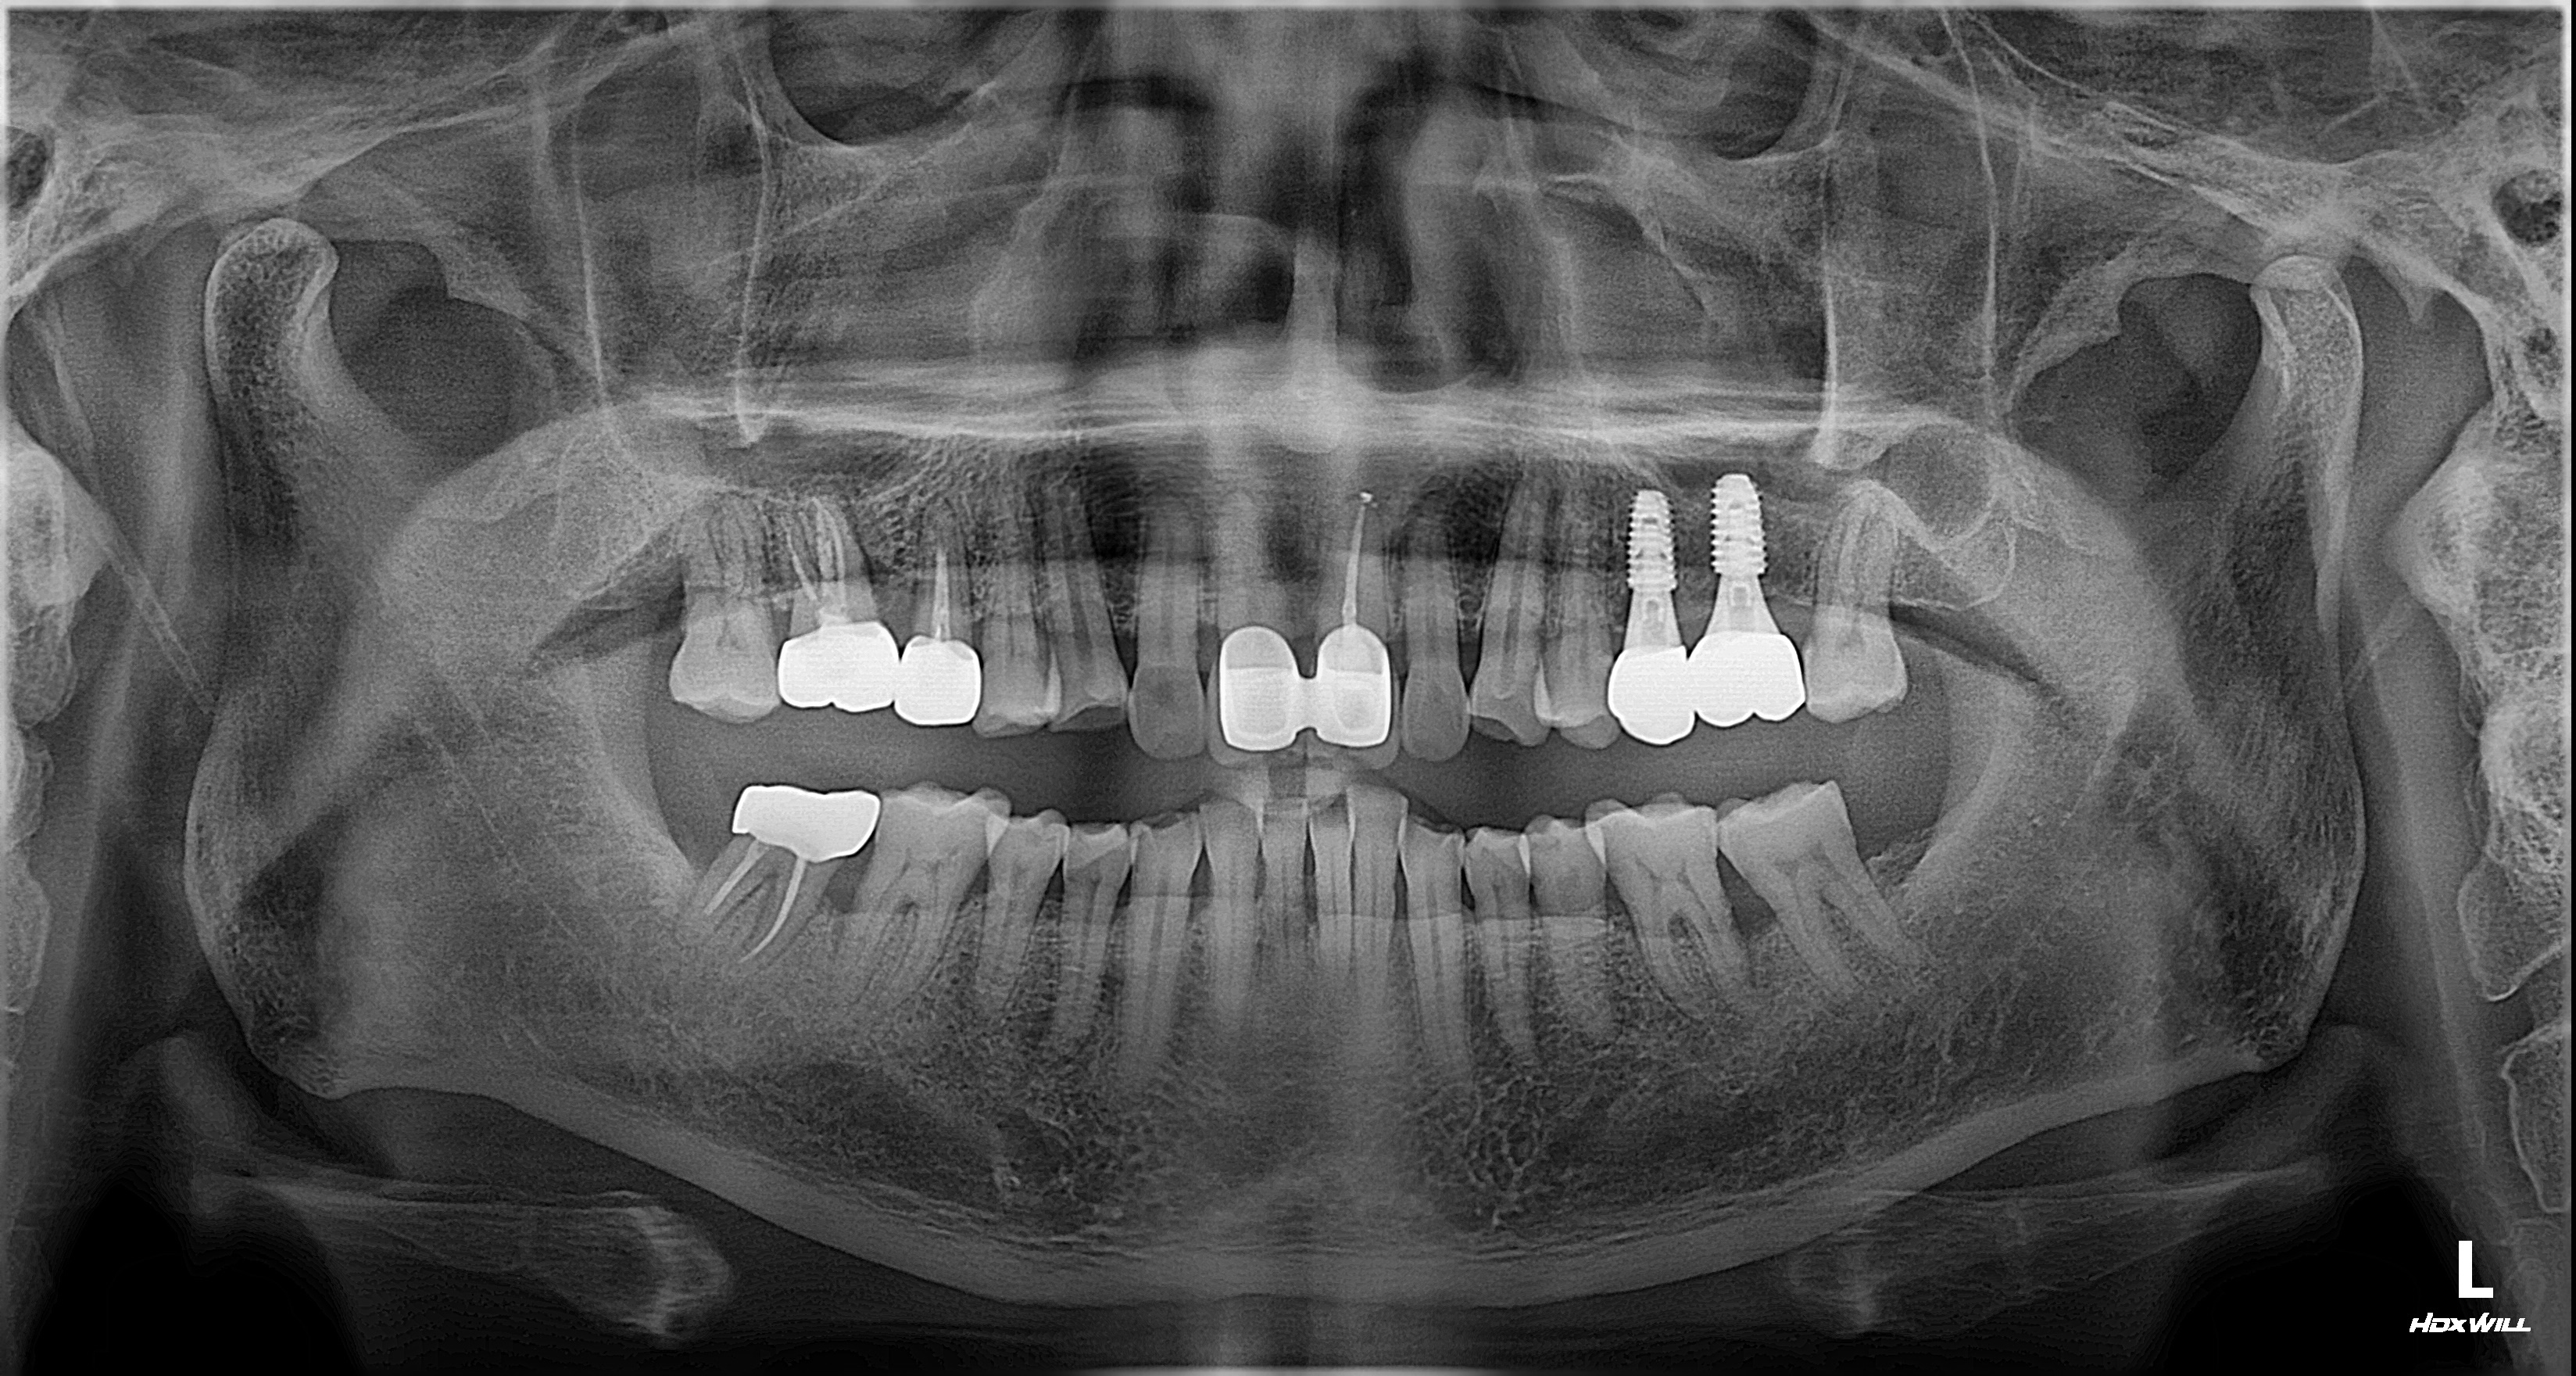

2026년 3월 18일, 최종 보철물까지 모두 체결되어 치료가 종료된 후의 방사선 사진입니다.

발치부터 최종 완성까지 약 1년 2개월의 시간이 소요되었습니다.

의료진이나 환자 모두 치료 기간이 단축되기를 희망하지만, 인체의 뼈가 재생되고 티타늄 소재의 임플란트와 단단하게 골융합(Osseointegration)을 이루는 과정은 물리적인 시간의 단축에 명확한 한계가 존재합니다. 특히 염증 병소가 컸던 부위일수록 뼈의 재건을 충분히 기다리는 것이 부작용을 최소화하는 가장 확실한 방법입니다.